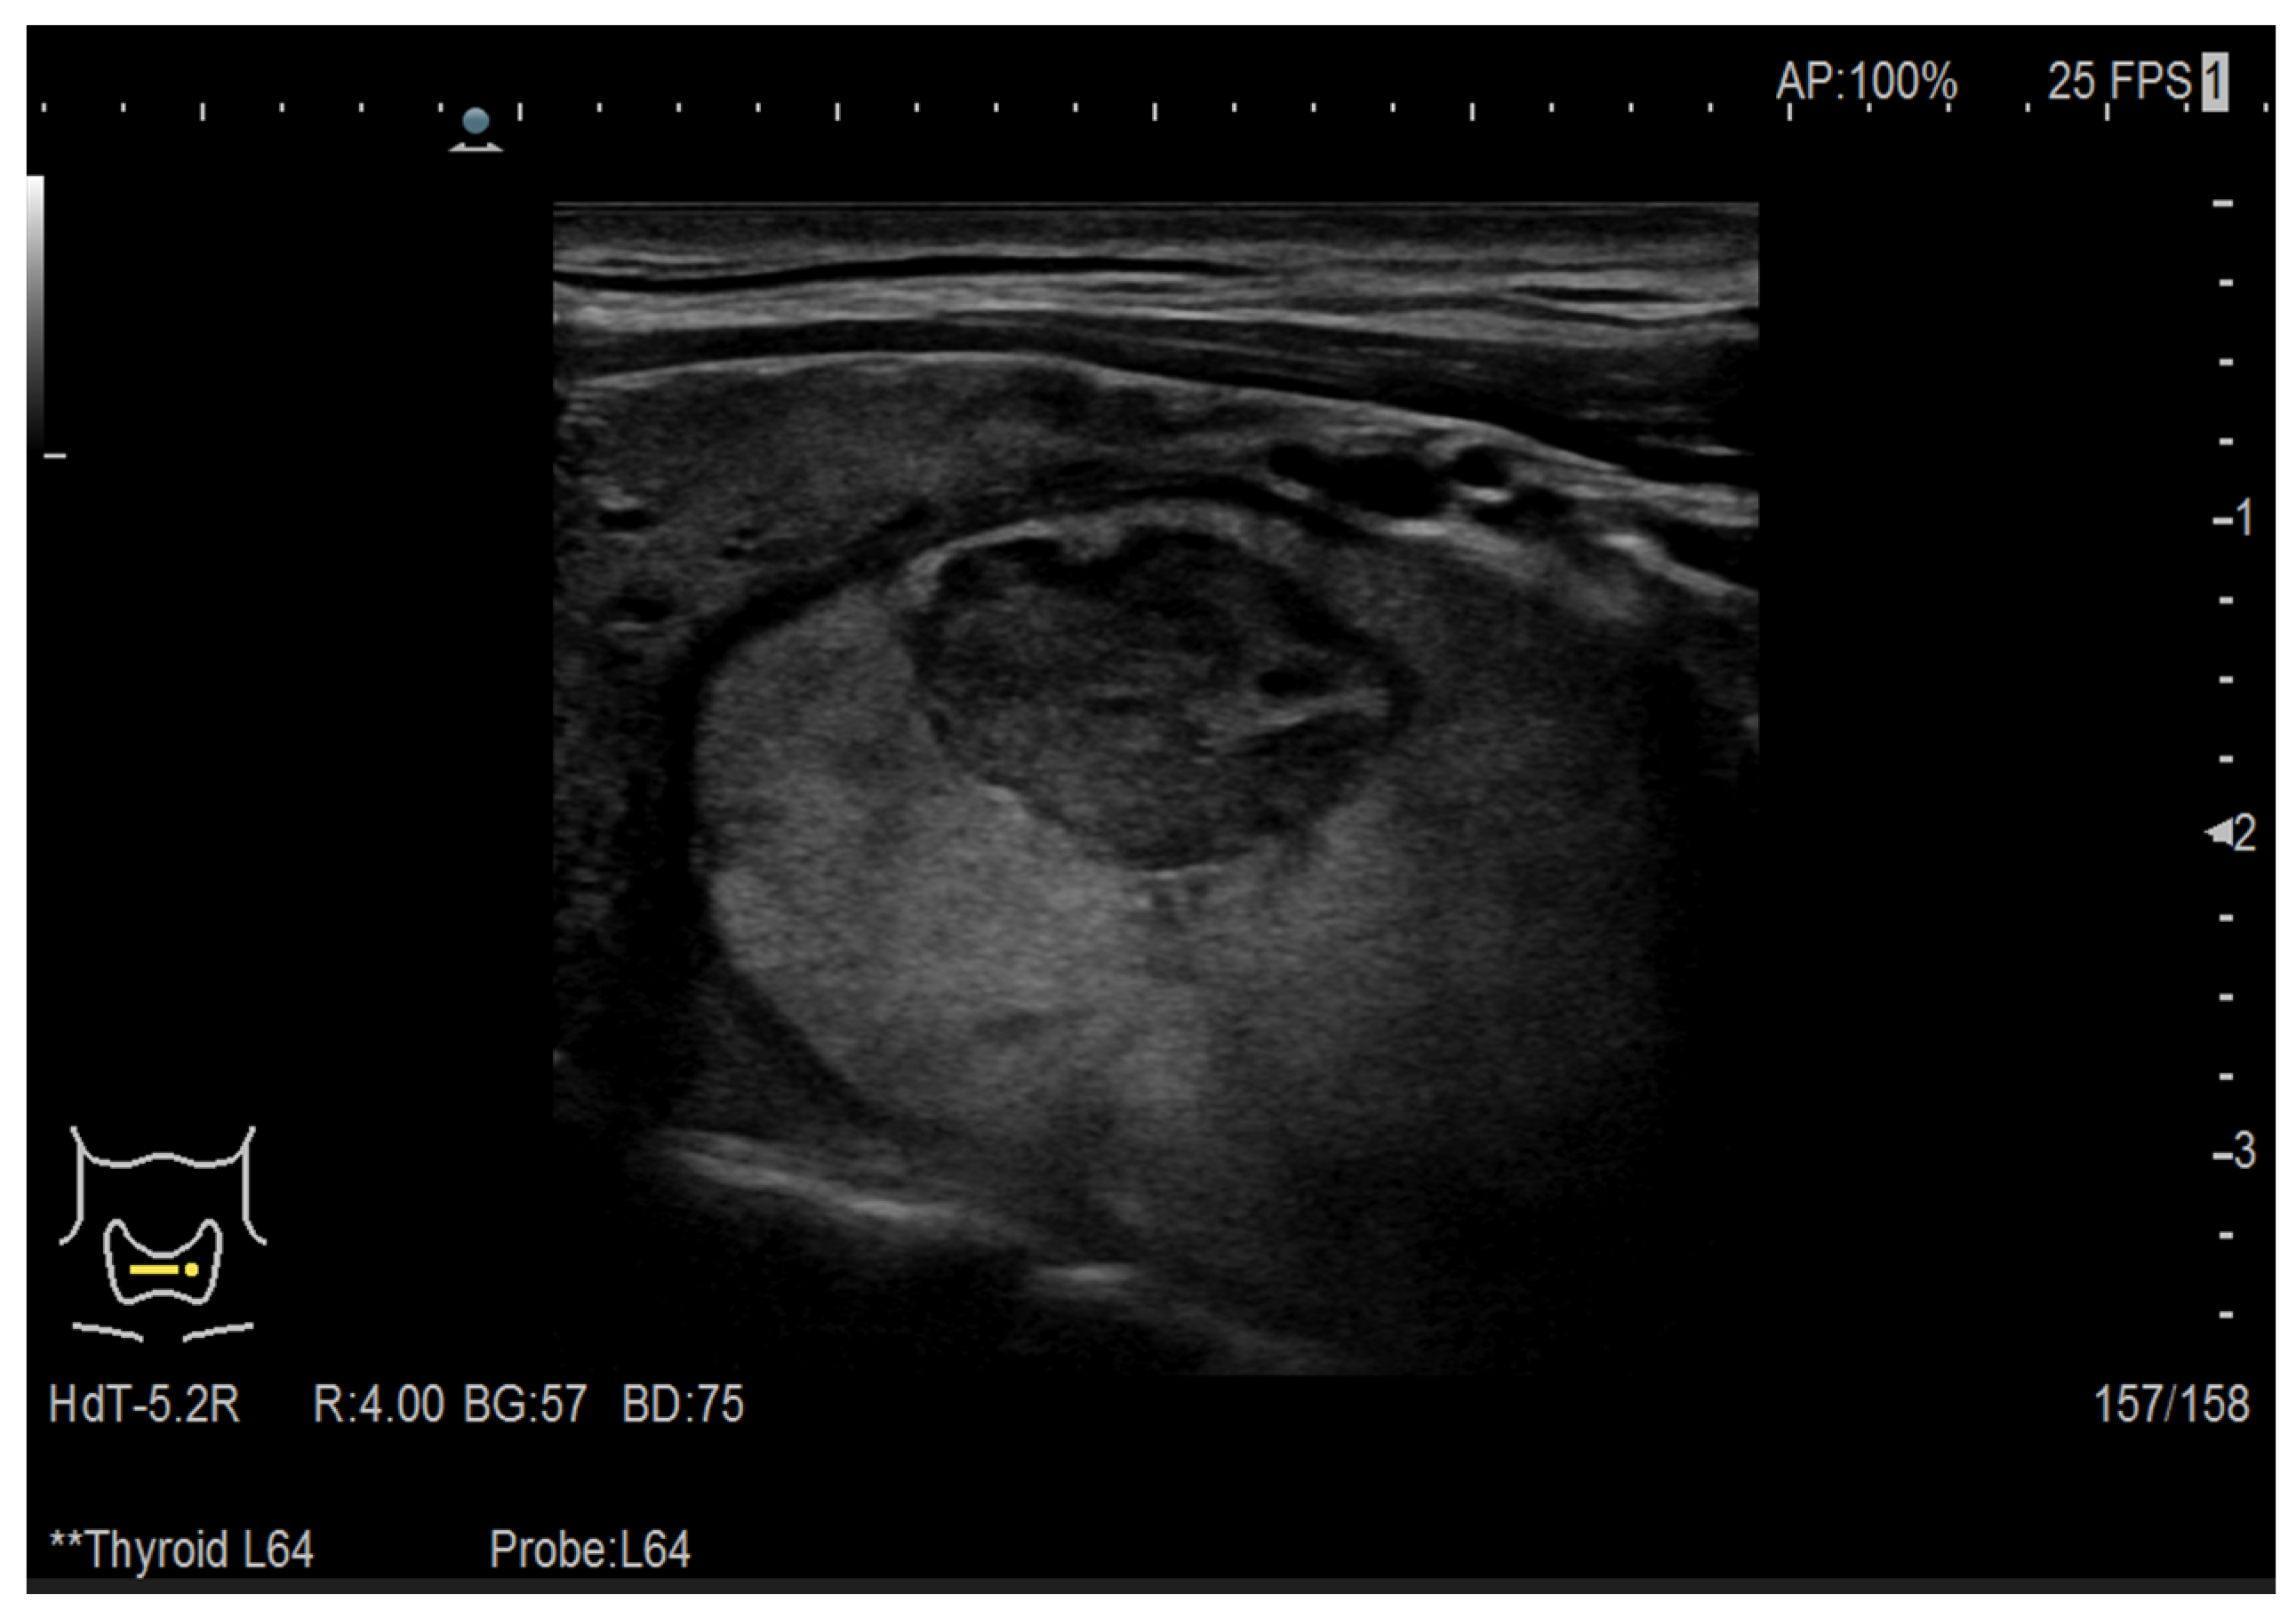

2.1. Ultrasound Images

2.1.1. The Data

3.1. Thyroid Nodule Diagnosis Based on Ultrasound Images: Binary Classification Problem Solved Using Convolutional Neural Networks